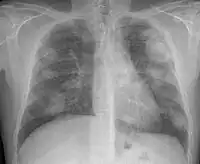

Complicated silicosis

Silicosis ILO Classification 2-2 R-R

For uncomplicated silicosis, chest x-ray will confirm the presence of small (< 10 mm) nodules in the lungs, especially in the upper lung zones. Using the ILO classification system, these are of profusion 1/0 or greater and shape/size "p", "q", or "r". Lung zone involvement and profusion increases with disease progression. In advanced cases of silicosis, large opacity (> 1 cm) occurs from coalescence of small opacities, particularly in the upper lung zones.

With retraction of the lung tissue, there is compensatory emphysema. Enlargement of the hilum is common with chronic and accelerated silicosis. In about 5–10% of cases, the nodes will calcify circumferentially, producing so-called "eggshell" calcification. This finding is not pathognomonic (diagnostic) of silicosis. In some cases, the pulmonary nodules may also become calcified.

- Complicated silicosis

- Silicosis can become "complicated" by the development of severe scarring (progressive massive fibrosis, or also known as conglomerate silicosis), where the small nodules gradually become confluent, reaching a size of 1 cm or greater. PMF is associated with more severe symptoms and respiratory impairment than simple disease. Silicosis can also be complicated by other lung disease, such as tuberculosis, non-tuberculous mycobacterial infection, and fungal infection, certain autoimmune diseases, and lung cancer. Complicated silicosis is more common with accelerated silicosis than with the chronic variety.